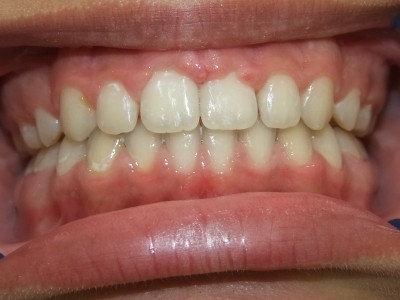

eindfoto